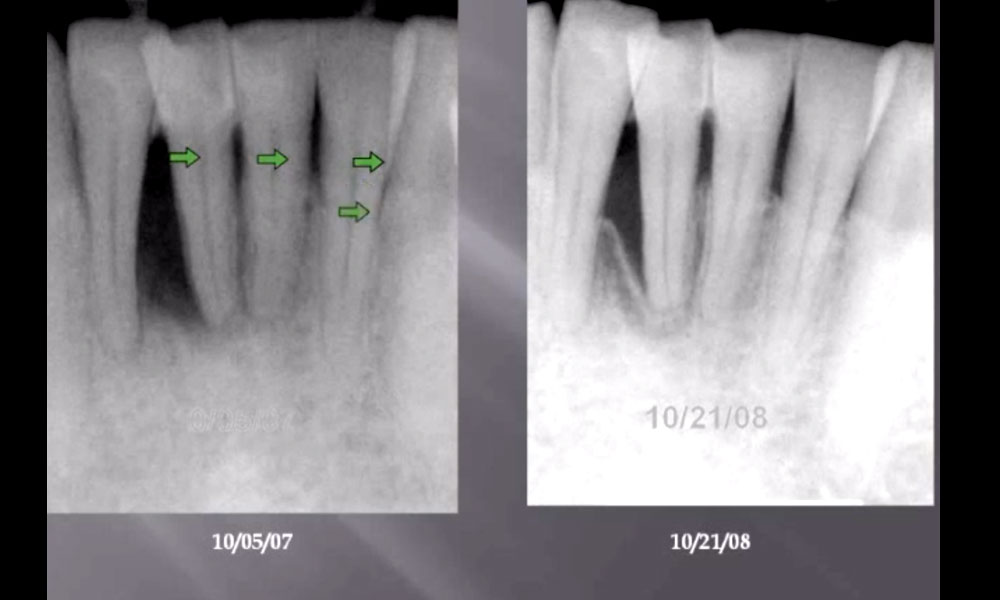

LANAP laser Periodontist Allen Honigman lecture. Dr shows before and after photos X-Rays and CT scans of patients that have had laser gum treatment with the Periolaser laser

LANAP laser Periodontist Allen Honigman lecture. Dr shows before and after photos X-Rays and CT scans of patients that have had laser gum treatment with the Periolaser laser